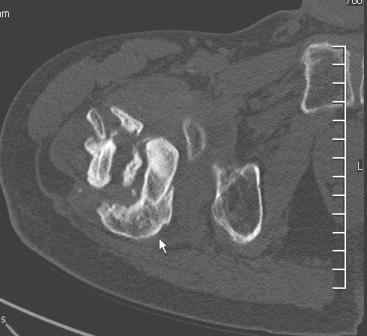

Больной Н. 44 года травма 1,5 года назад июнь 2008 года чрез-под вертельный перелом правого бедра. Во время лечения у больного развился алк. делирий, проводилось консервативное лечение перелома.

Беспокоят боли, укорочение конечности.Укорочение 3 см. Ногу поднимает, сгибание ограничено, ротационные движения в полном объеме.На КТ перелом сросся за счет костной мозоли.Что делать?

Уважаемый Глеб, боли из-за ложного сустава шейки бедра. Сращения там нет.

Уважаемый Глеб! Укорочение наверное побольше, да и наружно-ротационная установка скорее всего присутствует. Суставная щель прекрасная, головка живее всех живых. Ратую за подвертельную с латерализацией: исключает нарушение механической оси («исключает вальгус в коленe»), максимально удлиняет без натяжения m.iliacus. Для иллюстрации остеотомия-переделка (слава богу не автопеределка) у мужчины 65 лет.